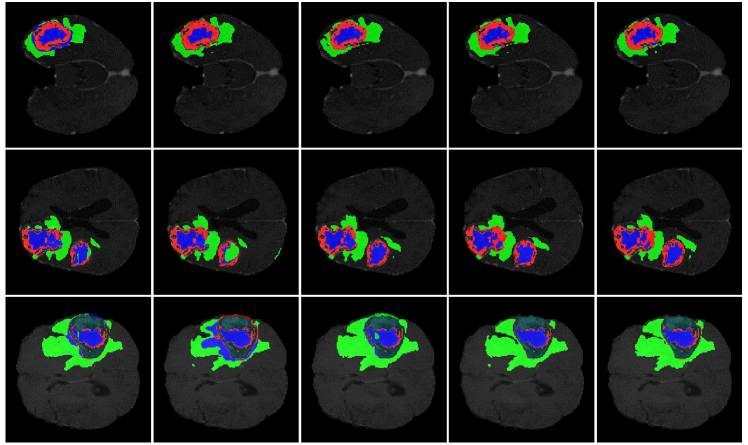

For qualitative analysis, the brain tumor segmentation results of various methods are shown in Fig. 3 for a visual comparison (more visual comparison on BraTS 2019 dataset can be seen at Sec. 6.1 in Appendix), including 3D U-Net[11], V-Net[27], Attention U-Net[29], and our Med-DANet. Since the labels for the validation set are not available, the five-fold cross-validation evaluation is conducted on the training set for all methods. It is obvious from Fig. 3 that our framework can delineate the brain tumors more accurately and generate much better segmentation masks with the powerful candidates as our dynamic options. Since we successfully take advantage of both CNNs and Transformer for different inputs, both local details and global context can be captured by our method to achieve accurate segmentation of tumors.

To further demonstrate the advantage of our proposed dynamic framework, we present more visualization of brain tumor segmentation results on BraTS 2019 for qualitative analysis in Fig. 7. The different methods utilized for visual comparison consist of 3D U-Net[11], V-Net[27], Attention U-Net [29], and our Med-DANet. It is clear from Fig. 7 that our framework can segment different kinds of brain tumors more precisely and generate much better fine-grained segmentation masks.